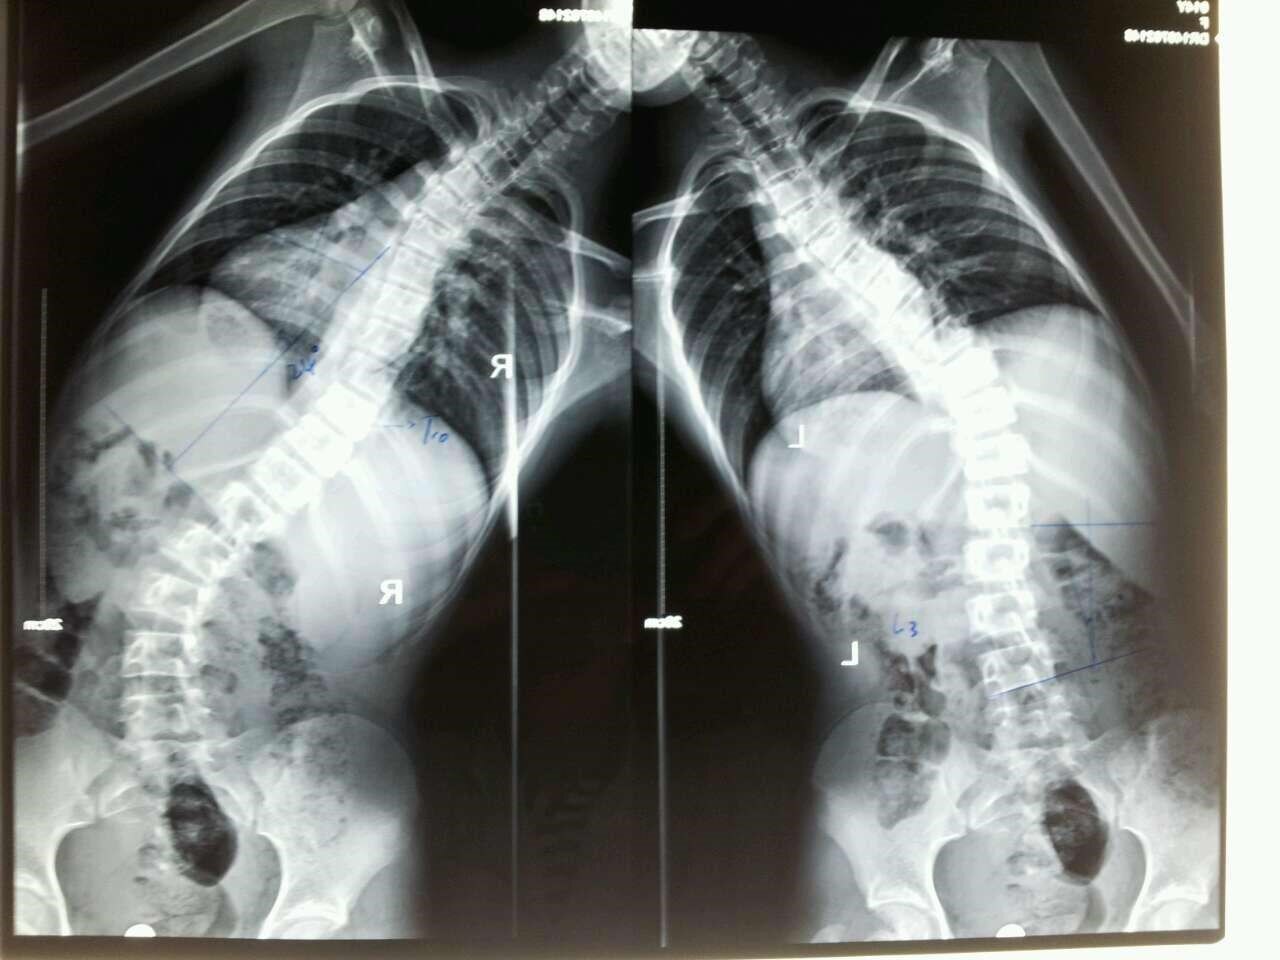

请问专家:胸腰椎侧s型变形该怎么处理更理想,是15岁女孩,谢谢!

图片尺寸720x960